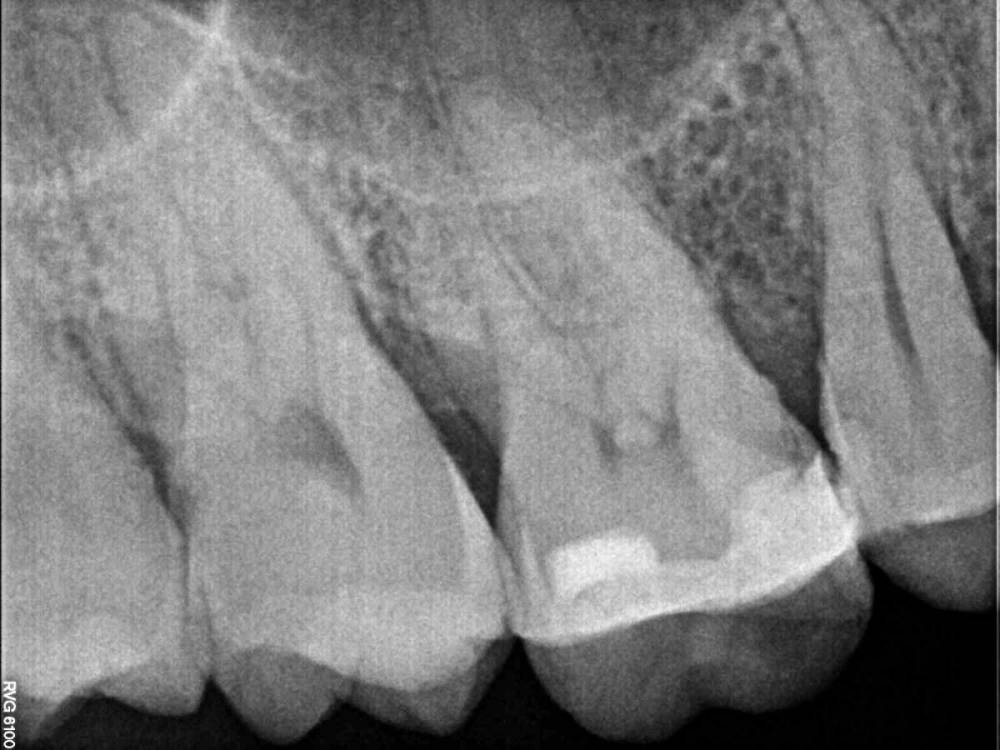

Jyuly Опубликовано 30 мая, 2023 Поделиться Опубликовано 30 мая, 2023 Добрый день! 4 года назад установила керамическую вкладку E-MAX на "живой" зуб (предлагали на выбор пломбу или вкладку, как более долговечный и надежный вариант). 4 месяца назад вкладка начала "гулять", терапевт осмотрел, сказал, что она треснула + кусочек небольшой откололся. Была у ортопеда в марте, он сказал после осмотра и свежей ортопанорамы от февраля этого года (свежего прицела не было) что, велика вероятность, зуб придется депульпировать. Скажите, пожалуйста, можно ли по снимку сказать (одному из них 2 года, другому точно не знаю, ~3-4) степень вероятности депульпирования зуба? Что это за "шарик" внутри? Несколько дней, как зуб начал беспокоить, точнее, не сам зуб, а выше, челюсть ноет, отдает в область глаза и уха. Может, это и не от этого зуба боли, между 7 и 8 кариес по снимкам. Хороший терпевт, которого мне посоветовали, в отпуске до 29 июня, я и не понимаю, какого специалиста мне искать спешно - терапевта, для пломбирования каналов или ортопеда для установки новой вкладки. Помогите, пожалуйста, просто крик души! Москва Ссылка на комментарий

Jyuly Опубликовано 31 мая, 2023 Автор Поделиться Опубликовано 31 мая, 2023 4 часа назад, Carioznik сказал: Нет Думаю, нужно начать с ортопеда, чтобы он определил план действий по этому зубу. (либо будет делать сам , либо к терапевту сначала отправит) Вот ортопед меня и направил к терапевту. По его мнению (а он видел зуб воочию) скорее всего его нужно будет депульпировать. Он считает, что лучше треснувшую вкладку выпилить терпевту, ибо, если это сделает он (ортопед), и опасения подтвердятся, он меня отправит с открытым зубом, что не есть хорошо, лучше этого избежать. Дал мне терапевта своего, которого сам учил делать вкладки, и готов поручиться, а он в отпуске до 29 числа. Непросто найти хорошего специалиста самостоятельно. Я уже попробовала в прошлый раз (делала у другого ортопеда) - и вот результат. Вкладка, которая должна служить 10-15 лет простояла всего 4 года... Ссылка на комментарий

Carioznik Опубликовано 31 мая, 2023 Поделиться Опубликовано 31 мая, 2023 Ну варианты тогда такие: 1)ждать терапевта (что-то длинный у него отпуск.. ) и надеятся ,что зуб сильно не разболится (если конечно в нем причина Ваших болей) 2) искать, всё-таки, другого терапевта или ортопеда Ссылка на комментарий